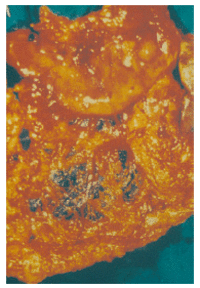

Melanoma accounts for 1-3 per cent of all malignant tumors. Except cutaneous, other less common melanomas include, among others, those in the GI tract. However, their primary or secondary nature is often difficult to establish. Referring to the stomach, scattered cases of primary melanomas have been reported in the literature. We report a case of a man with an ulcerated sub-mucosal mass at the antrum of the stomach, manifested with dull upper abdominal pain, nausea, vomiting, fatigue and anemia. This lesion was histologically proved to be melanoma. A detailed clinical and laboratory investigation revealed no primary site elsewhere. To our knowledge, very few cases of primary gastric melanoma have been reported. Our case is the fourth ever published and the first located at the antrum of the stomach. The debate upon the primitive nature of such lesions still persists. Thus, specific diagnostic criteria have been proposed.